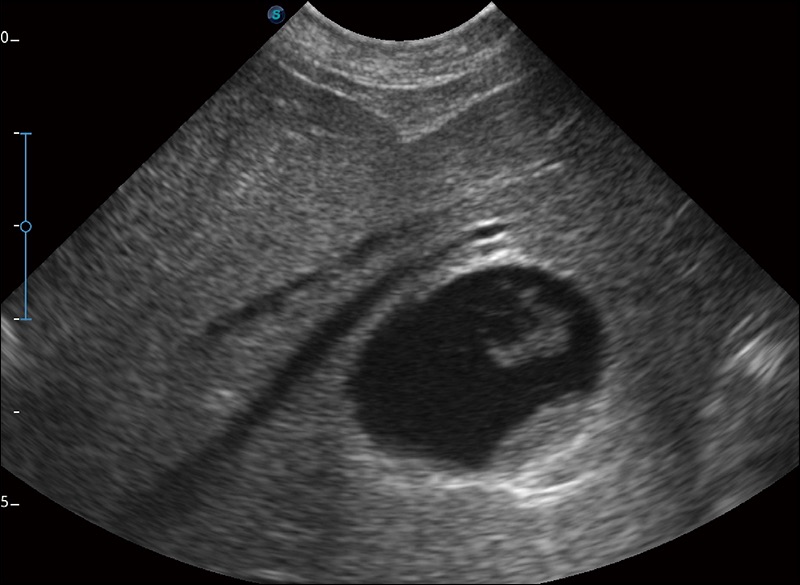

α1卓越的图像质量和便捷的工作流程,使每位宠物医生都能轻松扫查。其全面的兽用应用功能和紧凑型的结构设计,可以满足动物检查的多种需要。专业的预设检查模式和多领域测量软件包有助于为不同类型的动物提供检查, 让宠物医生能够出色的完成工作。

扩展成像

支持线阵和凸阵探头,一键操作即可获得更宽的图像视野

实时宽景成像

可实时观察感兴趣区域和病变位置